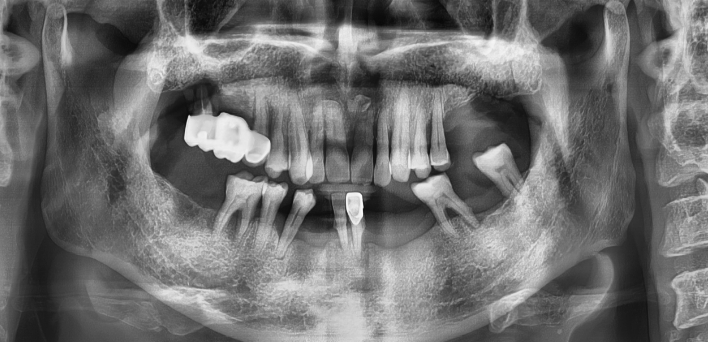

임플란트 : 손 ** 님 (50대)

Before Before

2020.02.30

환자 특징01무치악 상태

환자 특징02수년간 무치악으로 지내심

임플란트가 불가능할것이라

생각하고 내원

위, 아래 6개씩 식립

디지털 풀아치 임플란트